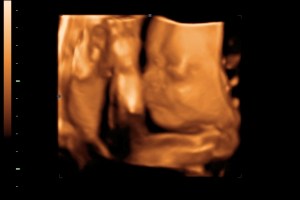

Etter mye om og men og trykking og styring fikk vi vekket han såppass at han tok bort armene fra ansiktet littegrann, så sovnet han igjen. Vi fikk ikke så mange bilder av den enkle grunn at det ikke var noe å se. Vi fikk noen filmklipp, men det er jo ikke noe som skjer på dem heller, så jeg så ikke poenget med å skrive dem over på disk. Vi fikk 2 greie bilder av ansiktet, that’s it.

Men jeg syns vi skulle fått kommet tilbake å ta nye bilder, for det var ikke verdt pengene. Vi visste jo at lille gullet hadde det bra, så var ikke det jeg hadde forventet. Jaja… Får håpe familien ikke blir like skuffet som jeg for at jeg ikke har noe å vise frem når jeg kommer hjem om noen dager.. Jeg legger ved det bildet som er det eneste som ble bra så får dere se gutten vår! Han er i alle fall lik pappa’n sin! 🙂